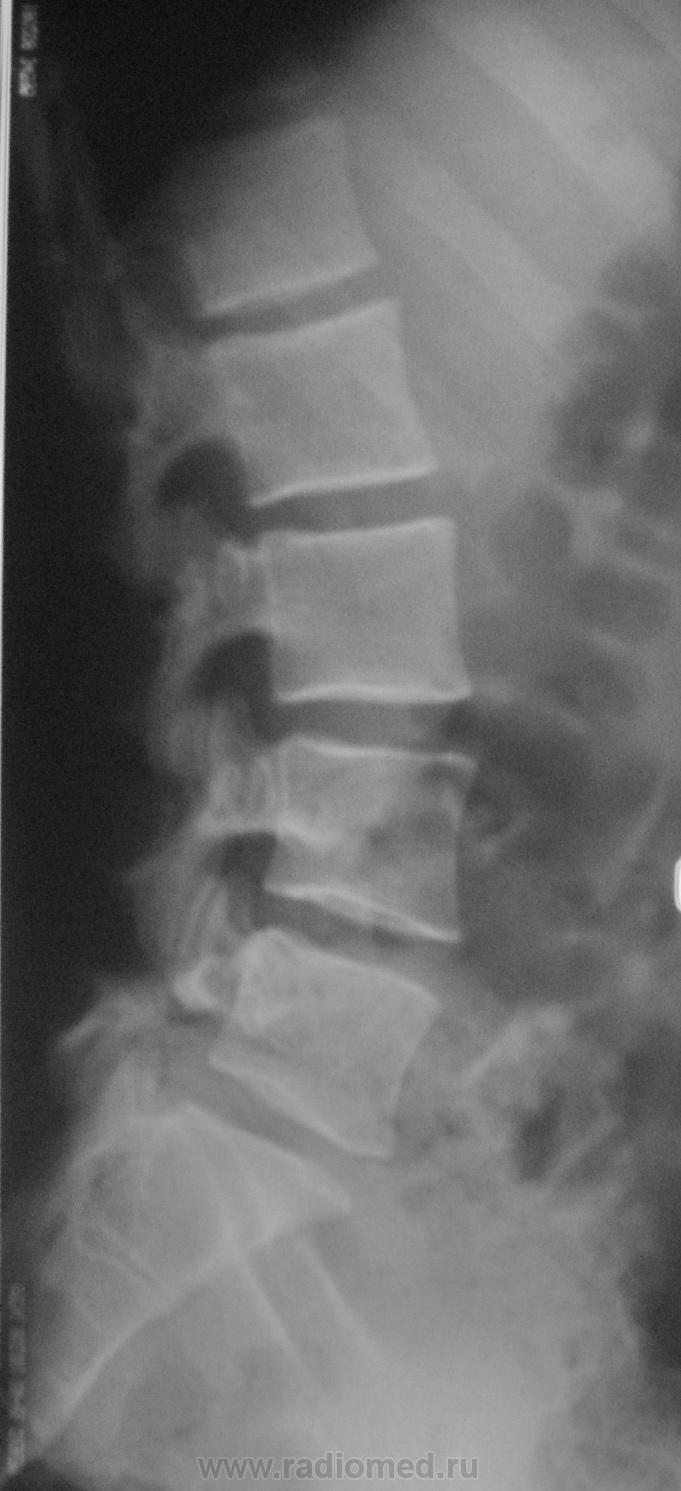

Пол пациента: Женский пол Тип патологии: Врожденная патология Область исследования: Скелетно-мышечная система Методы исследования: Rg Молодая женщина пришла на снимок поясничного отдела. Другая женщина, которая занимается рукопашным боем, обратилась с жалобами на боли в пояснице, после неудачного броска. https://radiomed.ru/sites/default/files/styles/case_slider_image/public/user/712/sl274202.jpg?itok=nrVgJub5 https://radiomed.ru/sites/default/files/styles/case_slider_image/public/user/712/sl274211.jpg?itok=ON6uvgKI https://radiomed.ru/sites/default/files/styles/case_slider_image/public/user/712/sl274212.jpg?itok=NmuMvaE1 https://radiomed.ru/sites/default/files/styles/case_slider_image/public/user/712/sl274213.jpg?itok=nP2dg6tE ID:18475 Пт, 27/01/2012 - 18:10 #1 Фаина Не на сайте Был на сайте: 2 года 11 месяцев назад Зарегистрирован: 14.12.2008 - 16:51 Публикации: 323 В первом случае, кроме остеохондроза и несросшихся апофизов, честно говоря, ничего критичного" не увидела. А во втором случае, не спондилолиз ли в L5?! Пт, 27/01/2012 - 18:17 #2 Наталия Не на сайте Был на сайте: 8 лет 7 месяцев назад Зарегистрирован: 30.07.2008 - 13:24 Публикации: 538 Во втором случае вероятнее спондилолиз. Пт, 27/01/2012 - 18:25 #3 Глазков Игорь А... Не на сайте Был на сайте: 9 месяцев 1 неделя назад Зарегистрирован: 19.12.2008 - 20:41 Публикации: 1597 Шморля в каудальной части тела позвонкаТ12 Прийди к Себе Пт, 27/01/2012 - 21:15 #4 И.Бондаренко Не на сайте Был на сайте: 3 дня 7 часов назад Зарегистрирован: 13.09.2011 - 22:55 Публикации: 9206 Случай №1. Грыжа Шморля Т12, несросшиеся апофизы L2,5 или обызвествившиеся грыжи дисков. Случай №2. Спондилолиз дужки L5. Ср, 01/02/2012 - 21:08 #5 Natalja Не на сайте Был на сайте: 13 лет 10 месяцев назад Зарегистрирован: 27.01.2012 - 22:08 Публикации: 4 Глазков Игорь Артурович wrote: Молодая женщина пришла на снимок поясничного отдела. Другая женщина, которая занимается рукопашным боем, обратилась с жалобами на боли в пояснице, после неудачного броска. В первом случае смущает L2, травмы не было? Чт, 02/02/2012 - 14:35 #6 Глазков Игорь А... Не на сайте Был на сайте: 9 месяцев 1 неделя назад Зарегистрирован: 19.12.2008 - 20:41 Публикации: 1597 травму отрицает Прийди к Себе

В первом случае, кроме остеохондроза и несросшихся апофизов, честно говоря, ничего критичного" не увидела. А во втором случае, не спондилолиз ли в L5?!

Случай №1. Грыжа Шморля Т12, несросшиеся апофизы L2,5 или обызвествившиеся грыжи дисков.